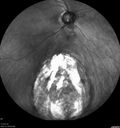

71 year old female with blurred vision from cataract. VA 20/63 OD, 20/40 OS. Left eye has large inferior coloboma.

Coloboma - Non Macular - Left Eye388 views71 year old female with cataracts. Left eye has inferior coloboma.00000